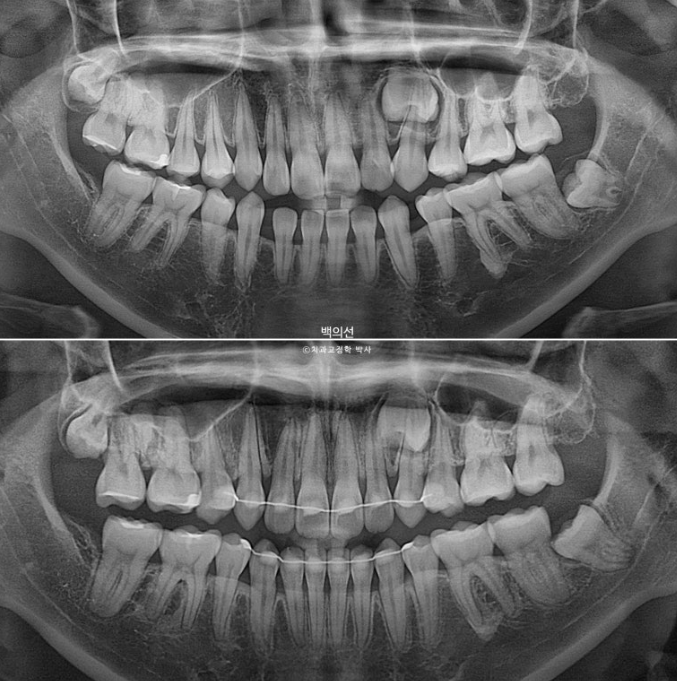

23.01~25.07

2년반 교정기간동안 매복치는 건드리지 않았고 그대로 잘 남아있습니다.

치근평행도는 좋습니다.

2년반의 기간동안 치근흡수는 일어나지 않았습니다.